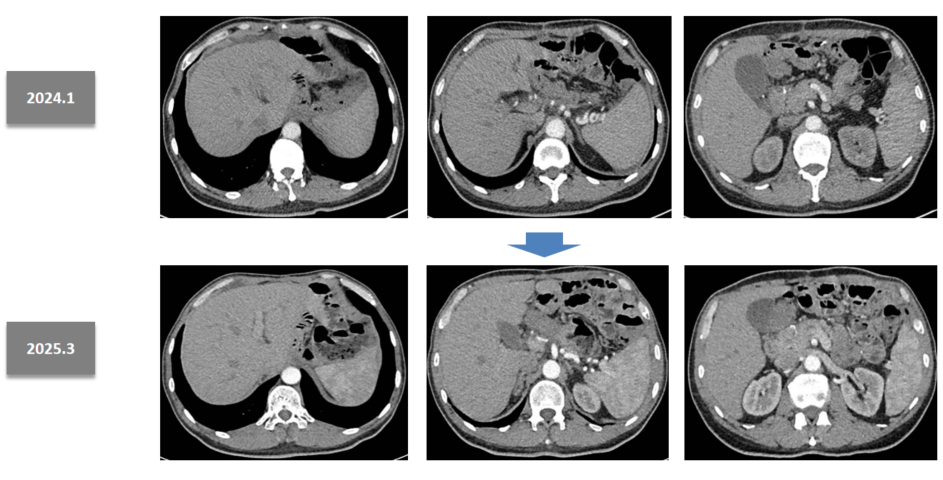

PET-CT(2023年9月):胃体及胃窦巨大占位,并提示广泛淋巴结转移。

930.7.png

图1 2023年9月PET-CT结果